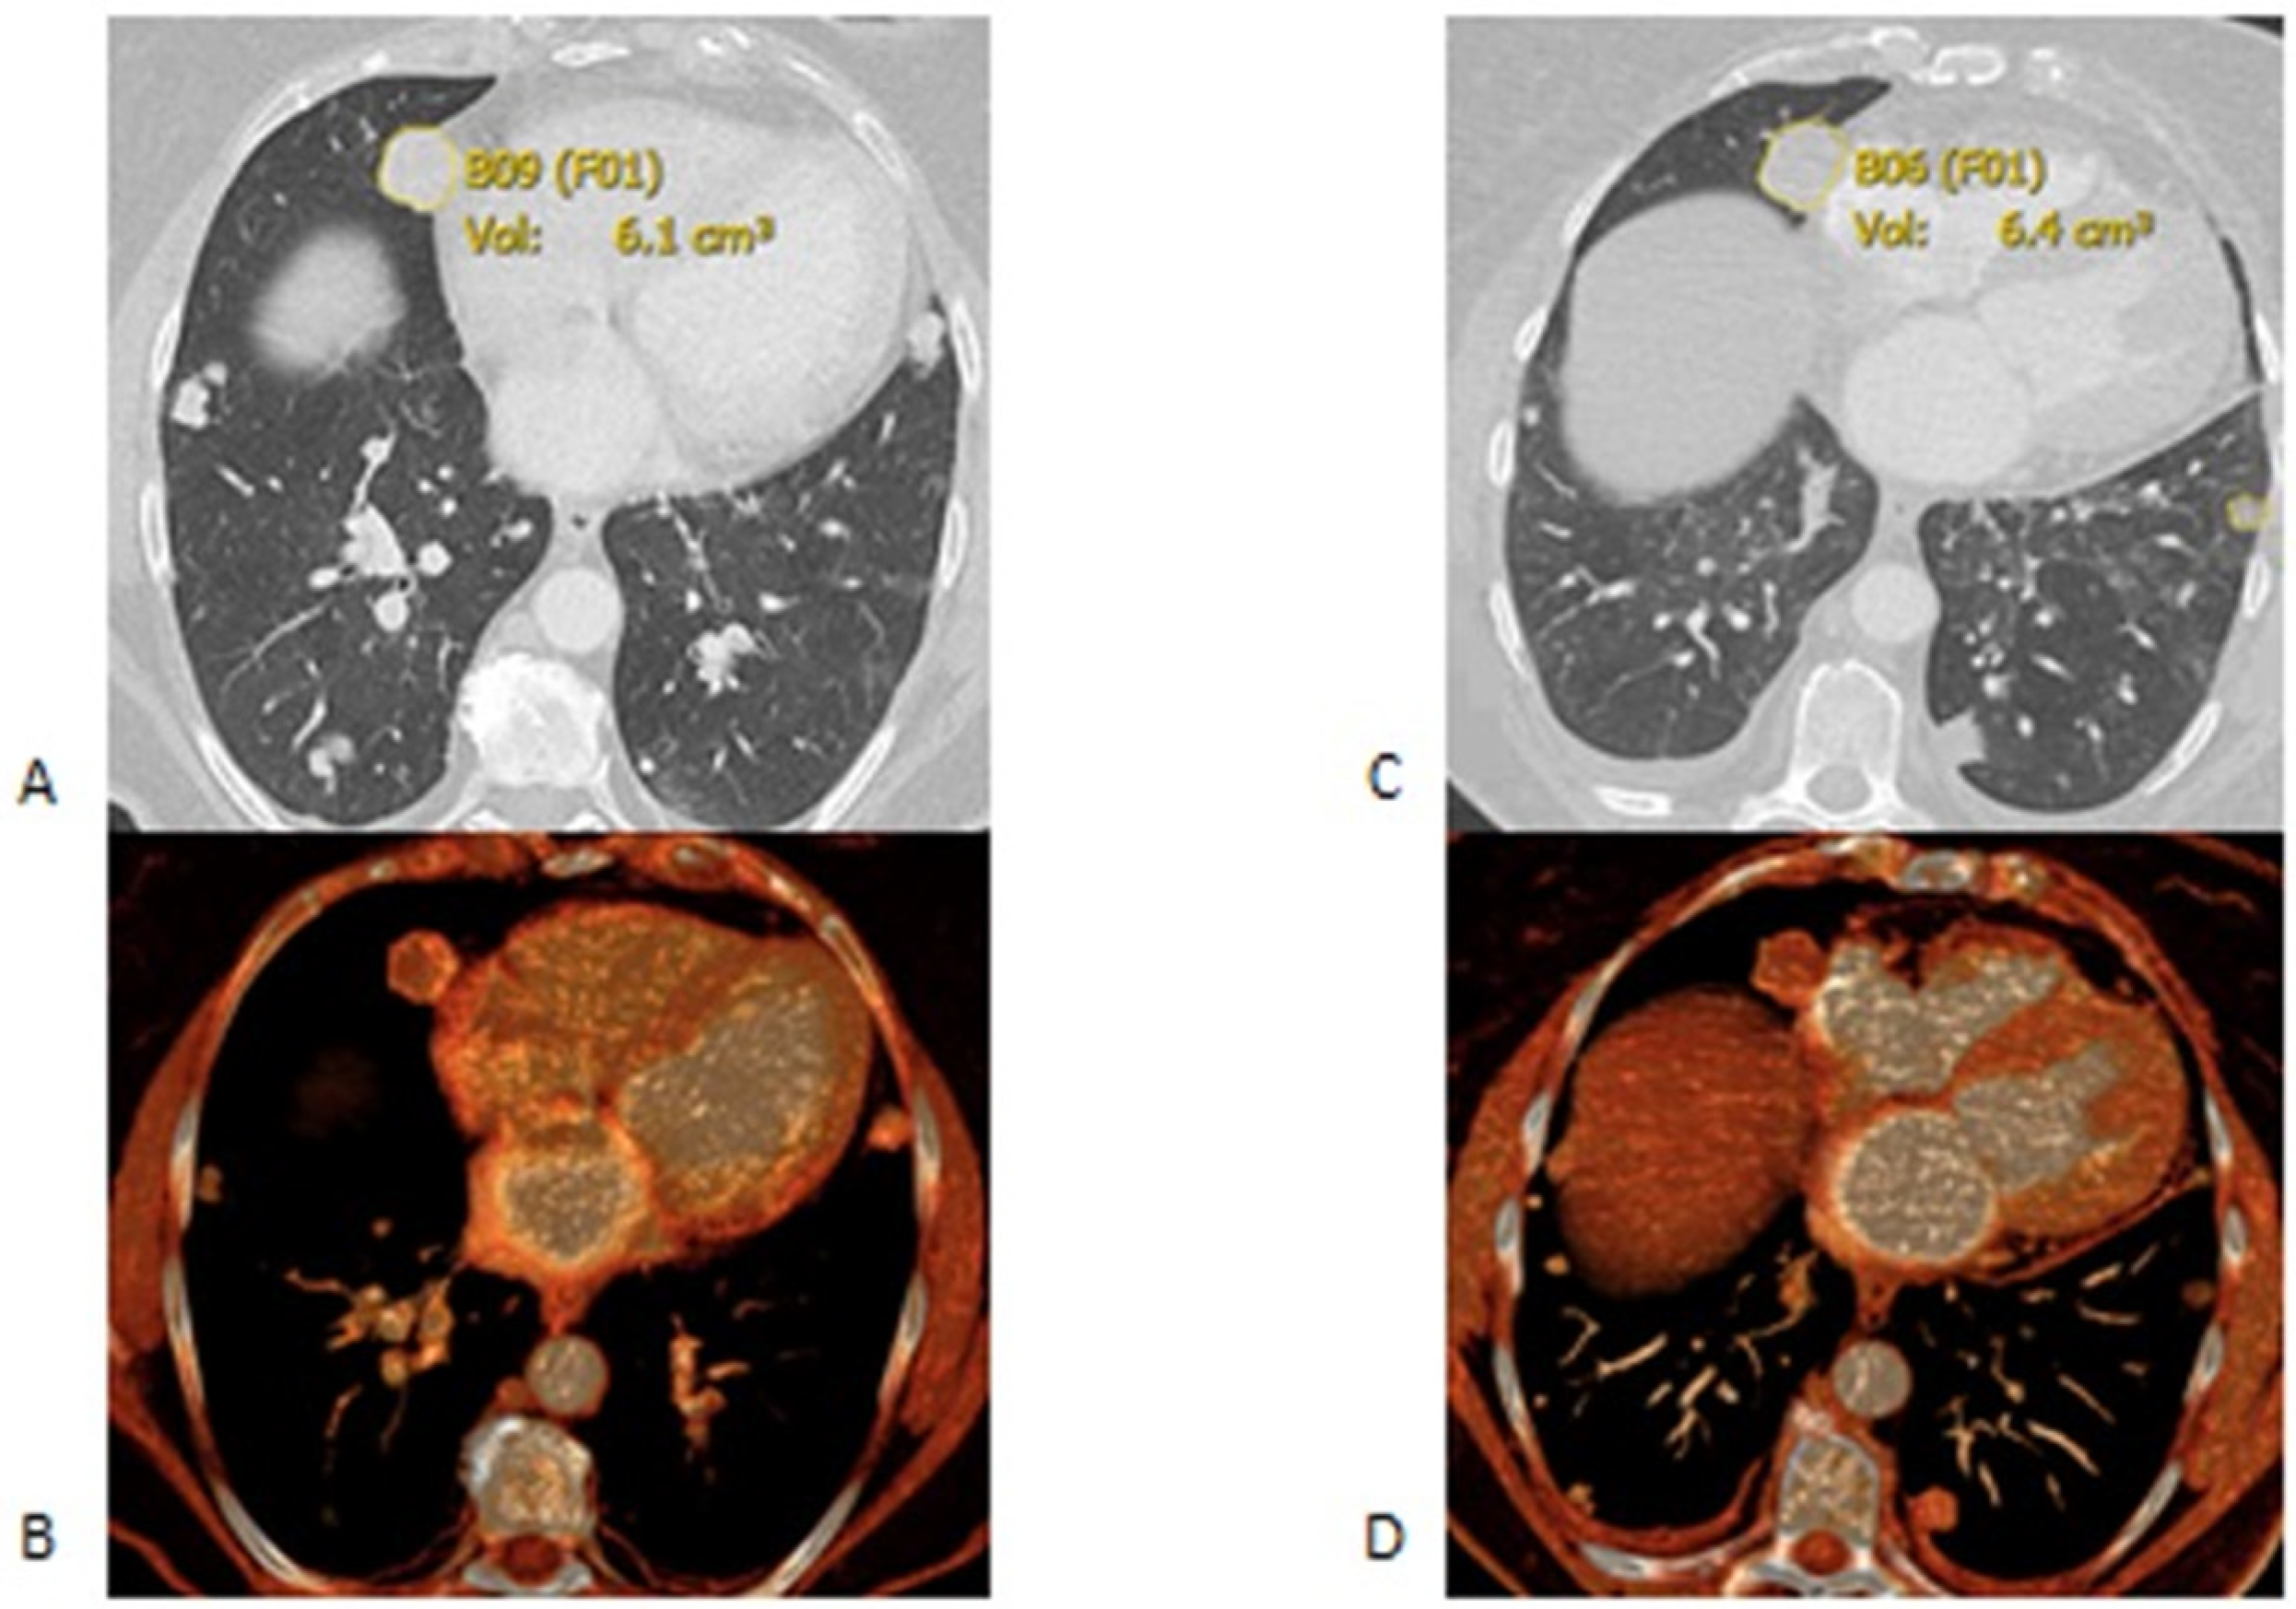

2.2. Imaging Analysis